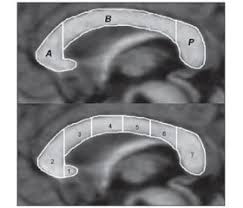

Штучний інтелект нагадав мені що, міст між правою та лівою півкулею називається corpus callosum.

Не знаю чи доречно буде додавати, що corpus callosum має три відділи : передній відділ, тіло та

задній відділ (A,B,P)